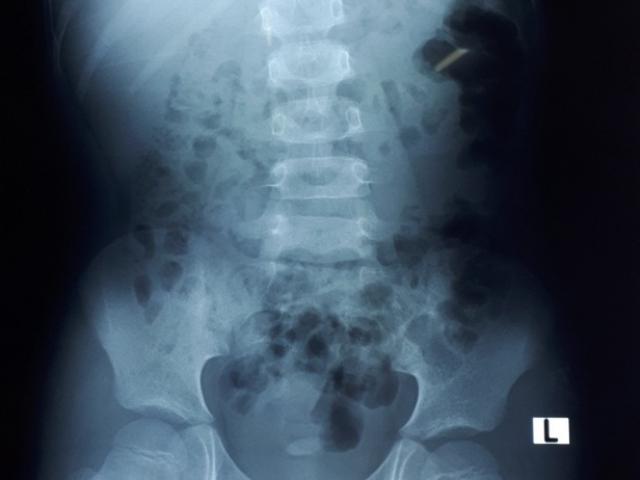

Ảnh minh họa